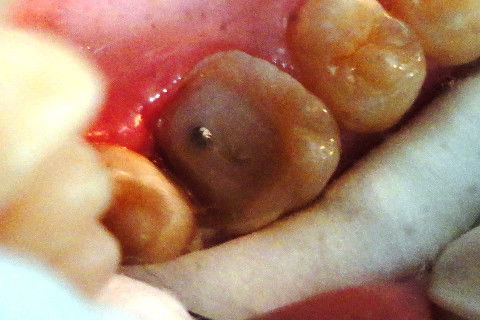

Cimentação de Pino Metálico Pré- Fabricado

Preparo para ONLAY

Paciente M. A. P do sexo masculino, 12 anos compareceu ao consultório odontológico com o elemento 16 apresentando extensa destruição coronária, e sentindo dor. Foi Observada a necessidade de realizar endodontia, sendo ela executada com Instrumentação Rotatória utilizando o aparelho X-Smart (Dentsply) e obturação pela técnica de condensação lateral. Para suportar a restauração (ONLAY) foi necessária a cimentação de pino metálico pré-fabricado (produzido por: FKG Dentairi), sendo cimentado com Fosfato de Zinco (Cimento LS- Vigodent) e realização de núcleo de preenchimento em resina composta, seguido do preparo para ONLAY.